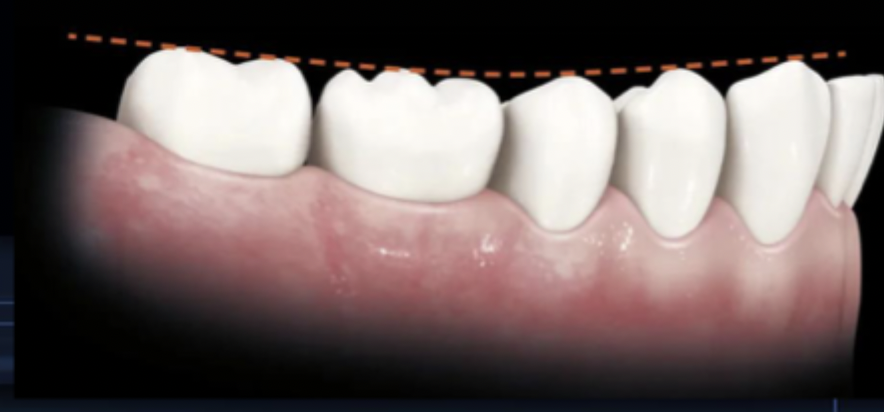

what is the curve of spee?

the curvature which begins at the tip of the canines and follows the buccal cusps of the posterior teeth, when viewed from the facial; continues up the arch through the condyle

<p>the curvature which begins at the tip of the canines and follows the buccal cusps of the posterior teeth, when viewed from the facial; continues up the arch through the condyle</p>